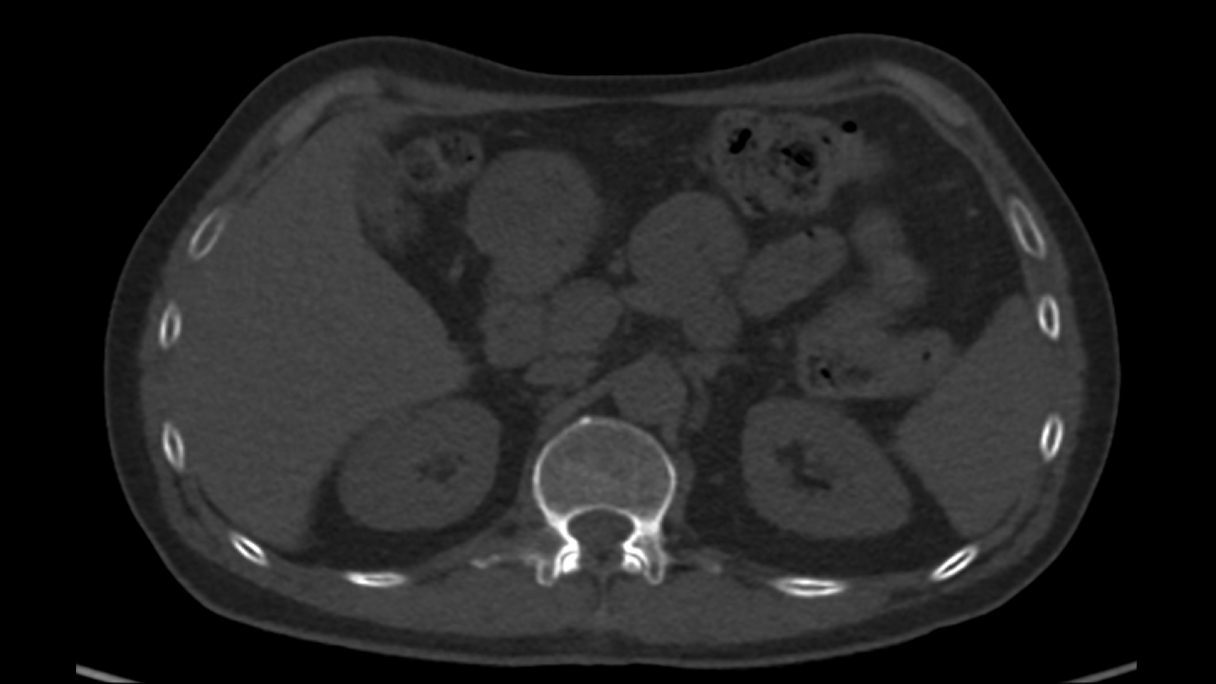

Casi clinici

Scopri come le tecnologie di imaging più innovative di GE HealthCare hanno giocato un ruolo chiave nella diagnosi di condizioni cardiache complesse.